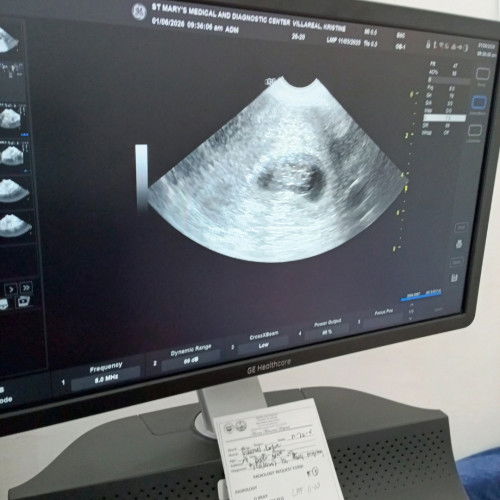

But Now im pregnant at my 8 weeks and 6 days with heart beat na thank you lord.

Kakaultrasound ko lng po ngayun at ang nakita lang po ay gestational sac with yolk sac and no fetal heart beat.. ganun po ba tlaga as a first time preggy.hindi ko alm kung babubuo po siya kayu po in your pregnancy .Anong pong weeks nio na laman na my heartbeat na si baby ninyo? #everyone